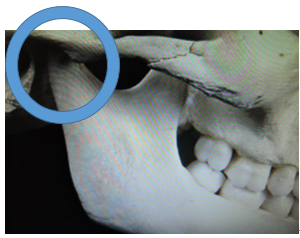

この写真の顎関節は小学校5,6年の形です。

顎関節の前方部の隆起が毎月、毎月成長していきます。

この為に、下顎骨を前方に適応させることが難しくなり上顎前突(出っ歯)の症状が突然目立ってきます。

この時期に矯正歯科医院を受診される人が増えてきます。

当矯正歯科医院ではこの時期に永久歯が萌え揃っていれば、治療を開始します。

この為に下顎骨を前方に適応させることが難しくなり、上顎前突(出っ歯)の症状が突然目立ってきます。

当矯正歯科医院ではこの時期に永久歯が萌え揃っていれば治療を開始します。

小学校5,6年

小学校2,3年